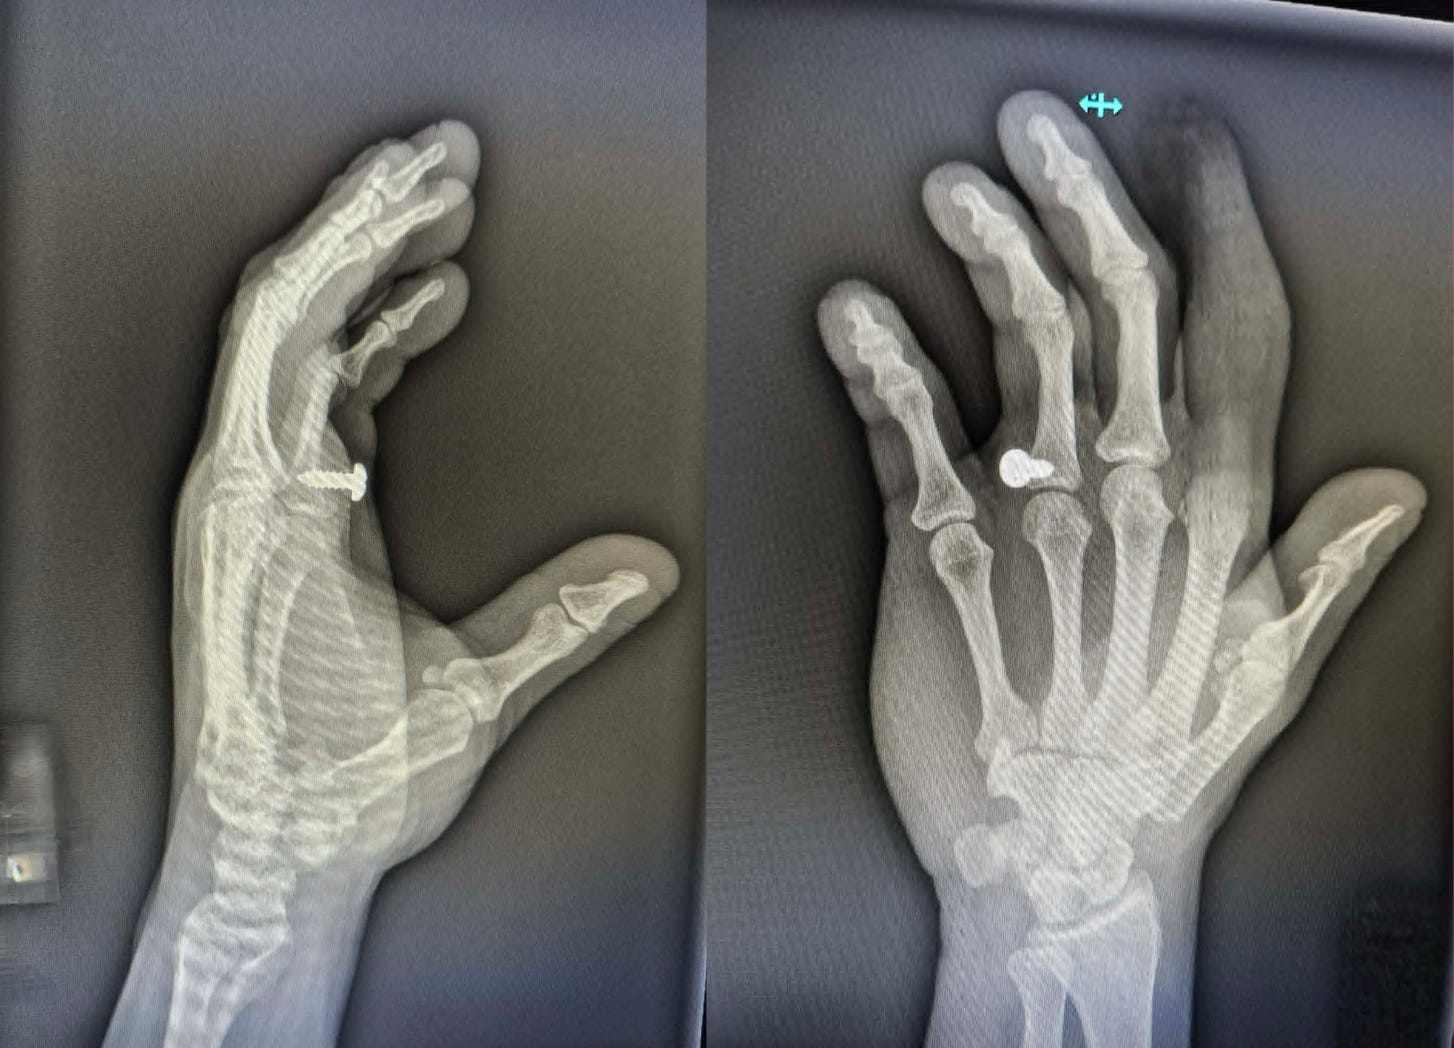

I got to go to the emergency room TWICE in the past week! Relax, it wasn’t for me, though it was for two people I love very very much. The first person shall remain nameless in the interest of privacy, though he is fine and home and it’s all good. The second was my husband, Zach, who on Sunday afternoon shot a sheet metal screw through his hand while using an impact driver to put up a flagpole on our front porch so we can fly the United Federation of Planets flag I got him for Christmas last year. Don’t ask how, exactly, that happened, only know that you shouldn’t use power tools with shooting or slicing or otherwise potentially dangerous capabilities if you are angry, annoyed and distracted by other things. Zach told me to write that specifically.

I am proud of the fact that we quite calmly (many many utterances of FUCK not withstanding) got in the car, drove to EMMC, got registered at the ER and then were seen almost frighteningly quickly by a doctor. Both ER visits this week were surprisingly speedy, in fact. Two seasons of “The Pitt” have prepared me to wait hours to see a doctor even if you have, I don’t know, a golf club through your chest or ebola or something. The x-rays showed he didn’t break any bones, and the doc removed the screw from Zach’s hand with a screwdriver and it didn’t even bleed that much, and I had gone to the cafeteria to get water so I missed it (boooo). A follow-up with a hand surgeon a few days later revealed there was no nerve or tendon damage, which was the big thing we were worried about; just a big ol’ puncture wound, and damaged pride. Zach, to his credit, still went to work the next day and did everything one-handed. Zach told me to write that specifically, though I would have mentioned how much of a devoted, hard worker he is anyway.

The moral of this story is: don’t work angry or tired, and don’t shoot sheet metal screws through your hand. If you do decide to shoot a screw (or nail, or other similar object; your choice) through your hand, do it the way Zach did it and miss all the important things.